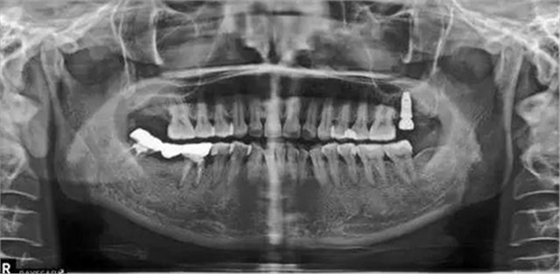

種植術后三個月復查X片。可見左上種植體已植入?;謴土己?。開始著手進行修復進行二期手術。